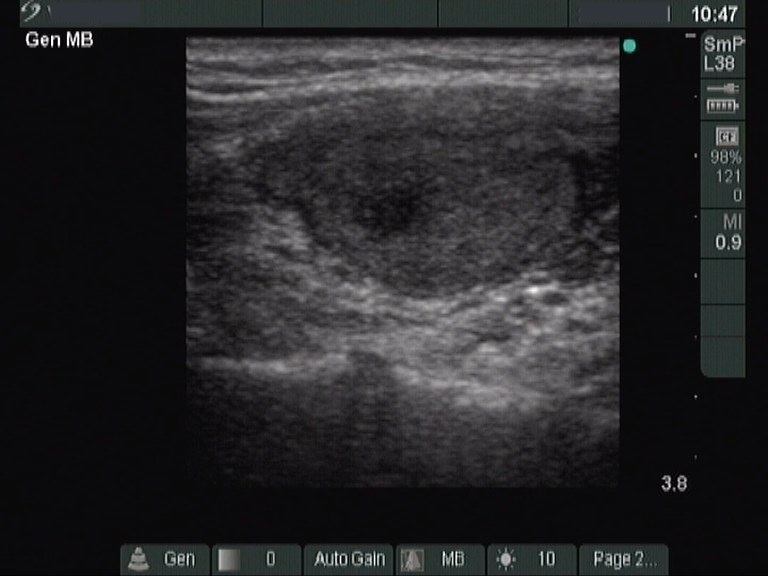

Chronic lymphocytic thyroiditis - Case 76. (ultrasonographic picture 2)

Right lobe, longitudinal scan.